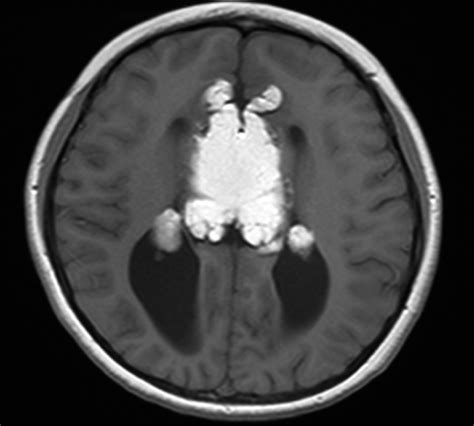

Son asintomáticos hasta en un 50% de los casos y cuando dan manifestaciones clínicas suelen cursar con epilepsia en ocasiones refractaria a tratamiento, cefalea o mareos. Se considera que el tratamiento quirúrgico está contraindicado en la mayoría de los casos por la alta morbilidad que conlleva la cirugía. En el TC presentan densidad grasa (-80 a -110UH) y en la RM intensidad de señal muy elevada en T1 y algo menos elevada en T2, usualmente sin realce tras la administración de contraste, aunque puede haber captación heterogénea, con atenuación de la señal en las secuencias con supresión grasa. Si se encuentran parcialmente calcificados pueden “florecer” en secuencias eco de gradiente.

Se describe el caso de una mujer de 38 años sin antecedentes personales de interés, diagnosticada de migrañas sin aura con una frecuencia de una crisis a la semana. A la exploración física no presenta focalidad neurológica ni otros datos de organicidad, salvo un episodio de pérdida de consciencia de segundos de duración, con recuperación total posterior, en relación con una de las crisis de migraña. La exploración neurológica no presentaba alteraciones. En la RM cerebral realizada se aprecia en los cortes sagitales una lesión curvilínea que rodea al cuerpo y al esplenio del cuerpo calloso de aproximadamente 8 cm de longitud, marcadamente hiperintenso en T1, hiperintenso en FLAIR con depósitos cálcicos en secuencia T2* eco de gradiente lo que produce un efecto de “florecimiento” del mismo. No se evidencian alteraciones vasculares en el estudio angio-RM. El cuerpo calloso presenta una morfología conservada. En el resto del estudio no se aprecian alteraciones de interés salvo un quiste de glándula pineal de 10 mm. Actualmente la paciente se encuentra en seguimiento por neurología, en tratamiento con rizatriptán de 10 mg para la migraña, con mejoría clínica y disminución de la frecuencia de las crisis.